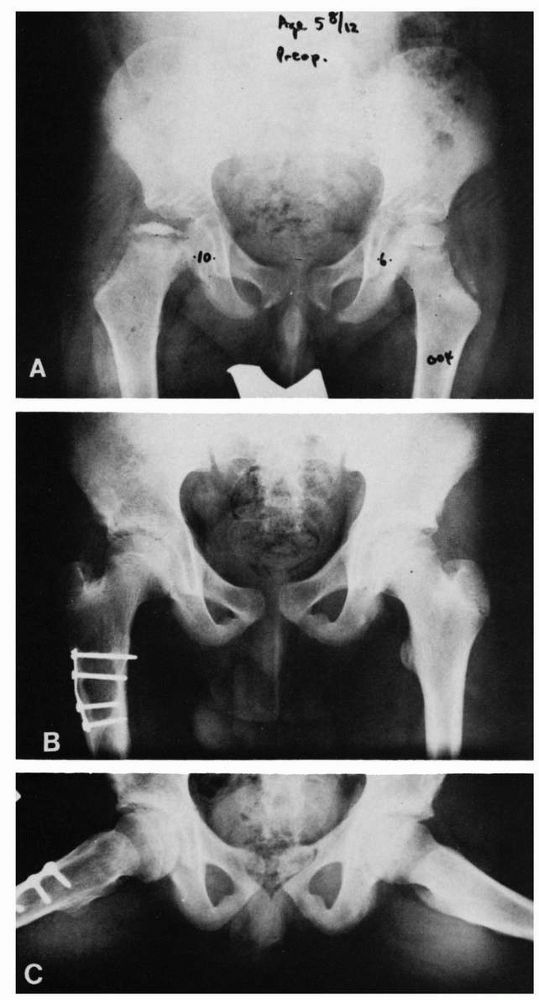

![]() |

|

FIGURE 15-25.

Varus/derotation osteotomy of Axer. This embodies the principle of containment of the diseased femoral head in the treatment of Legg-Calvé-Perthes disease, which is achieved by surgical means. Postoperatively, the child is permitted to walk with no restrictions, and the range of motion is full, so that the molding effect of the acetabulum on the femoral head is attained. (A) Severe involvement of femoral epiphysis in a boy 5 years 8 months of age, 9 months after onset of limp and pain in the left hip. (B) and (C) Ten years after varus/derotation osteotomy, excellent development of the femoral head is seen. (Courtesy of Dr. A. Axer) |

treatment are femoral osteotomy and innominate osteotomy. Abduction

containment offer the advantage of early mobilization and avoidance of

prolonged brace or cast treatment. Varus osteotomy with or without

rotation offers the advantage of deep seating of the femoral head and

positioning of the vulnerable anterolateral portion of the head away

from the deforming influences of the acetabular margin (Figure 15-25).